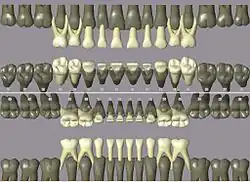

Codes, names, and usual number of roots: (see chart of teeth at Universal Numbering System)

- 11 21 51 61 maxillary central incisor 1

- 41 31 81 71 mandibular central incisor 1

- 12 22 52 62 maxillary lateral incisor 1

- 42 32 82 72 mandibular lateral incisor 1

- 13 23 53 63 maxillary canine 1

- 43 33 83 73 mandibular canine 1

- 14 24 maxillary first premolar 2

- 44 34 mandibular first premolar 1

- 15 25 maxillary second premolar 1

- 45 35 mandibular second premolar 1

- 16 26 54 64 maxillary first molar 3

- 46 36 84 74 mandibular first molar 2

- 17 27 55 65 maxillary second molar 3

- 47 37 85 75 mandibular second molar 2

- 18 28 maxillary third molar 3

- 48 38 mandibular third molar 2